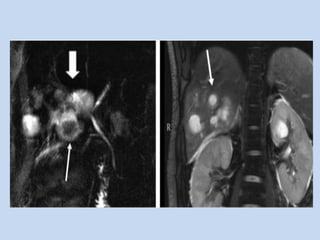

• In pancreatic carcinoma :

- “double duct sign” is observed in case of

pancreatic head mass. ( non- specific as it may

seen in chronic pancreatitis)

- MRA done in conjunction – assesses the

resectability..

APPLICATIONS • In pancreaticcarcinoma : - depicts the ducts obstructed by the pancreatic mass & localizes the obstruction to pancreas. - “double duct sign” is observed in case of pancreatic head mass. ( non- specific as it may seen in chronic pancreatitis) - MRA done in conjunction – assesses the resectability..